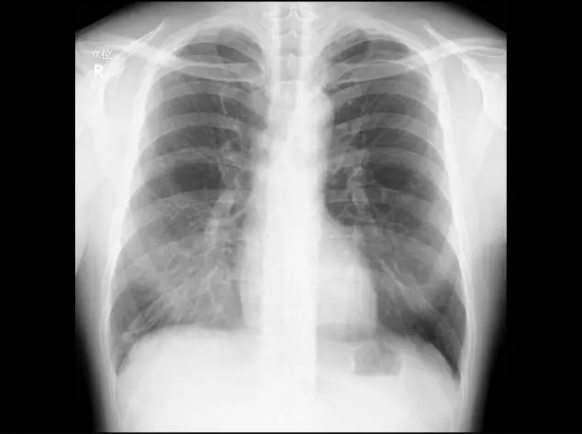

人工知能による画像診断とは深層学習によるアルゴリズム(計算手順)を用いて臓器の画像診断を行うものです。

レントゲンやCT検査のような画像診断においては、少なからず見落としが発生してしまいます。

検査を依頼した医師が画像の診断をしていることがほとんどです。 そのため、専門領域でない画像の診断においてはどうしても見落としの懸念がつきまといます。